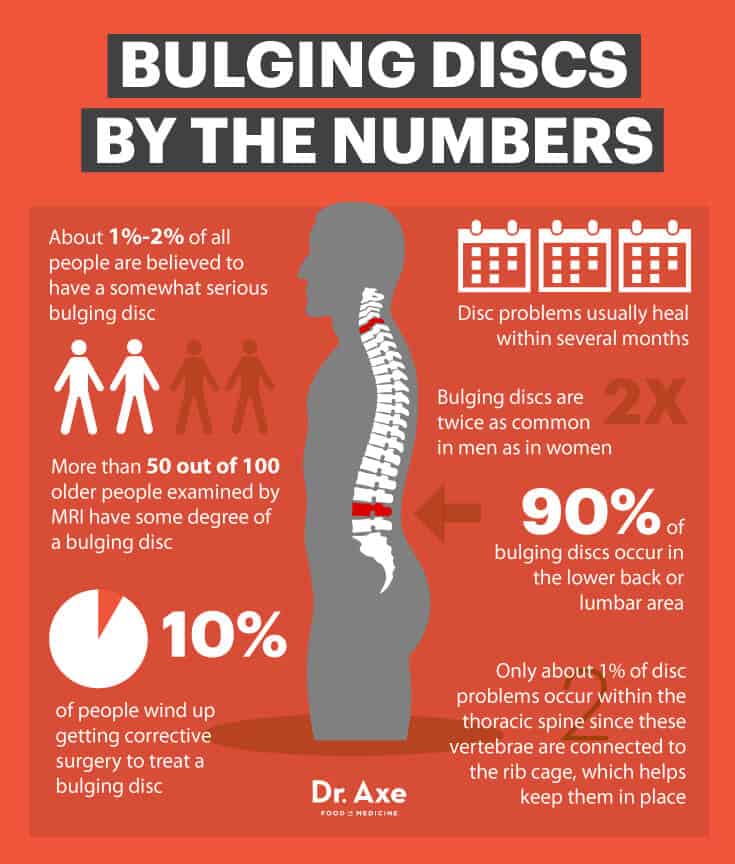

Bulging Disc & Back Pain: 7 Natural Treatments That Work – Dr. Axe

Bulging Disc & Back Pain: 7 Natural Treatments that Work – Dr. Axe

Bulging Discs And How You Can Slow Them Down